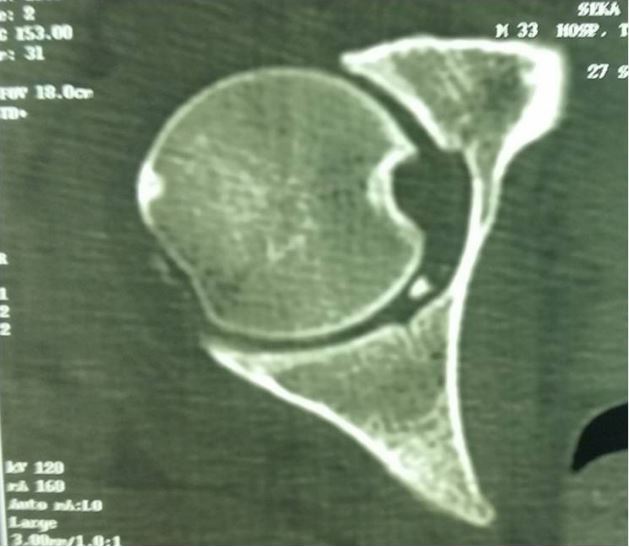

Plain X-rays confirmed a left subtrochanteric fracture and a right obturator dislocation of the hip with an intra-articular incarcerated fragment (Figure 3). Closed reduction of the dislocated hip and surgical treatment of the left subtrochanteric fracture by a Küntscher intramedullary nail; were performed the same day the patient was admitted. Post-reduction radiographs showed an articular gap widening with a defect in the superior lateral femoral head (Figure 4). A confirmation CT scan demonstrated an intra-articular incarcerated fragment (Figure 5). An arthroscopic extraction was warranted, but due to inadequate hospital equipment and patient financial hardship; the patient did not receive appropriate care. Fifteen months later; Mr. SA presented with a control X-ray showing early signs of coxarthrosis and peri-articular ossifications (Figure 6).

Figure 5: CT scan showing an intra-articular fragment (patient 3).